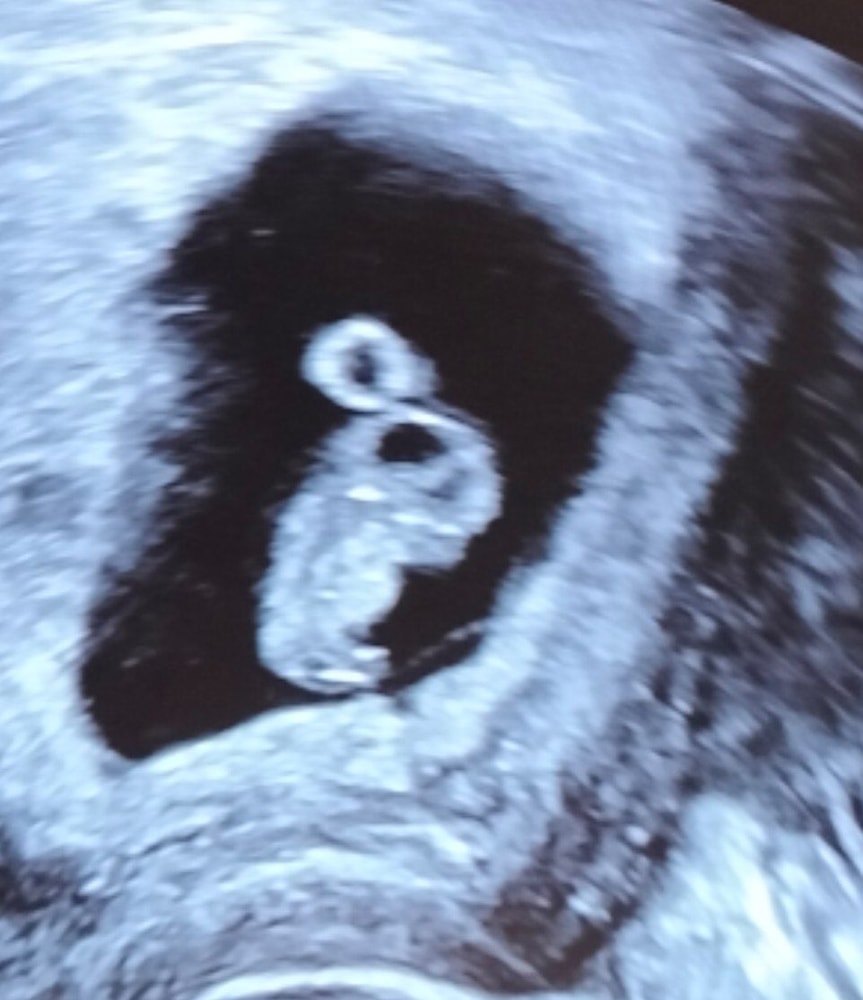

У нас всё хорошо. Размеры по сроку 8 недель, ЧСС 163 (27 июня в 6 недель было 94, узистка сказала "хотелось бы выше 100).

КТР 15 мм

Срок по месячным 8н6д

Ниже фото УЗИ.

Над головой это желточный мешочек?